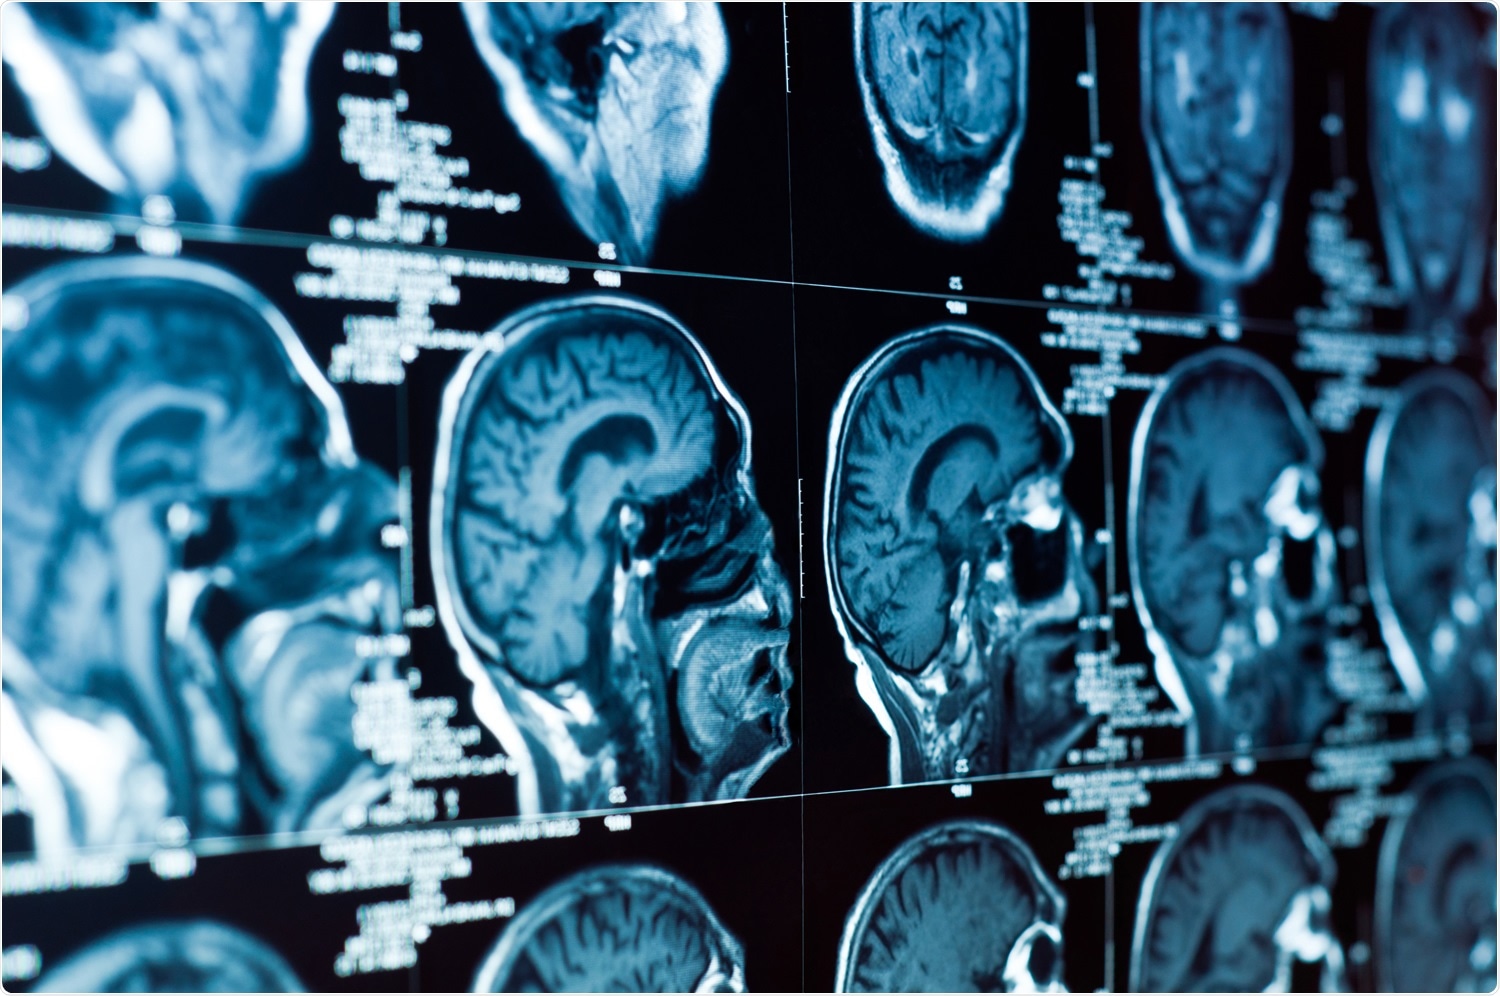

New research suggests pneumonia in COVID-19 patients is linked to viral-induced changes in the brain. MRI scans revealed 57.9% of severe acute respiratory syndrome coronavirus 2 (SARS-CoV-2) infected patients had recent brain lesions.

MRI scans showed brain lesions in 82.6% of patients. Additionally, about 57.9% of the identified brain legions were recent, suggesting the lesions were linked to SARS-CoV-2 infection. Only 41.1% of brain lesions were considered old.

Of the 57.9% with recent brain legions, 77.3% of these lesions were deemed “clinically significant.” These patients were the ones who had a stroke. Eight experienced a recent infarct, and five patients had a recent cerebral hemorrhage. In addition, four patients showed signs of global hypoxic-ischemic encephalopathy.

Five patients had MRI scans positive for nonspecific subcortical changes, suggesting white matter microangiopathy. Of these 5 patients, 2 were below the age of 50 and had nonfocal neurological manifestations and microangiopathic lesions. Laboratory evidence showed these patients had a history of viral infections, including MERS-CoV infection. The remaining 3 patients were older than 50 and had microangiopathic lesions associated with lacunar Infarcts.